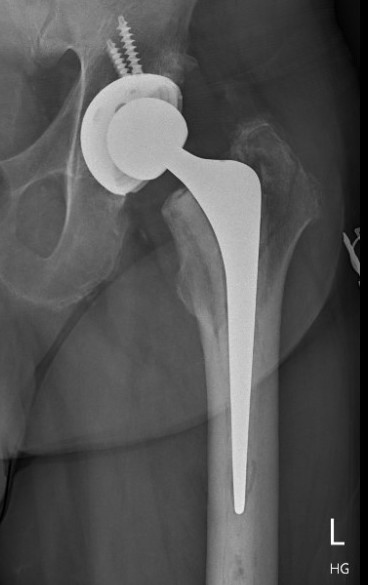

Fracture with stem subsidence around a polished tapered femoral stem treated with ORIF